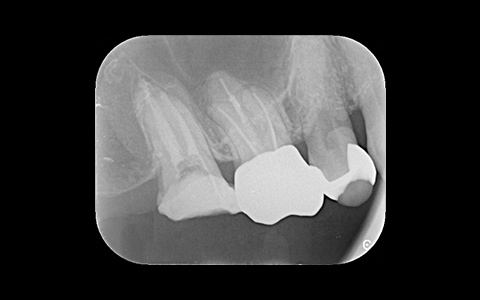

治療前

治療後

黄色い矢印の歯が治療前の対象歯です。レントゲンで観察すると、歯の根のお薬が充分には入っていないようです。

麻酔をして歯の中をマイクロスコープで観察すると、元々あった3つの根だけでなく「もう一つの4番目の根」があったのです。根管治療自体は容易に行えましたが、歯の中を明るく拡大できるマイクロスコープを持っていない歯医者さんでは見つけるのが困難だと思われます。この4つ目の歯の根を治療することにより痛みは消失し「抜歯してインプラント」になるという悪循環に陥らず済みました。根管治療はマイクロスコープを使って精密に、また丁寧に行えば歯を長く保たせることができる治療です。やはり神経自体を残すという選択が、歯の保存にとって一番良いということは間違いありません。

| 費用 | デンタルドック:55,000円 根管治療(奥歯):176,000円 MTAセメント:33,000円 歯の土台:33,000円 合計:297,000円 |

| リスク・副作用 | 治療中に一時的な咬合痛や冷温水痛、若干の歯肉の腫れ、発赤などを生じることがあります。また仮歯の時期には仮歯の脱離や破損の可能性、舌感などに違和感を覚えることがありますが、本歯に移行するまでに通常消失します。 ※すべて症例による違いや個人差があります。 |

※表示金額は全て税込みです。